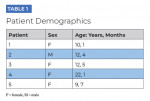

This practice-based study was designed to assess the effect of the Oral-B iO toothbrush and Targeted Clean brush head on patients' plaque accumulation and motivation to brush over a 9- to 14-week period in patients with fixed orthodontic appliances and a history of poor oral hygiene. The five enrolled patients ranged in age from 9 to 22 years, and all had active fixed orthodontic appliances. Additionally, all patients had poor oral hygiene, as measured with the Ortho Essentials Chairside Laminate Card (Procter & Gamble, dentalcare.ca)25 and defined as a score of 1 at the last two to three orthodontic appointments. Poor oral hygiene was signified by erythematous gingivae with spontaneous bleeding with the presence of oral biofilm (plaque). White-spot lesions and demineralization were also common concomitant findings. All patients formally consented to participate in the study and to try the novel O-R electric toothbrush (Oral-B iO). Patient demographics are summarized in Table 1.